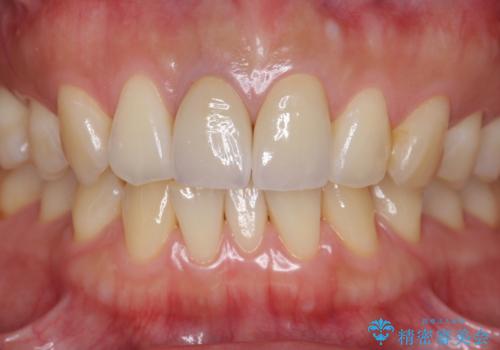

セラミック治療について

最終的なセラミッククラウンの精度・色調は非常に大事ですが、そこに至るまでの根管内環境の洗浄、ファイバーコアによる緊密な封鎖も長期的な予後に重要であると考えます。